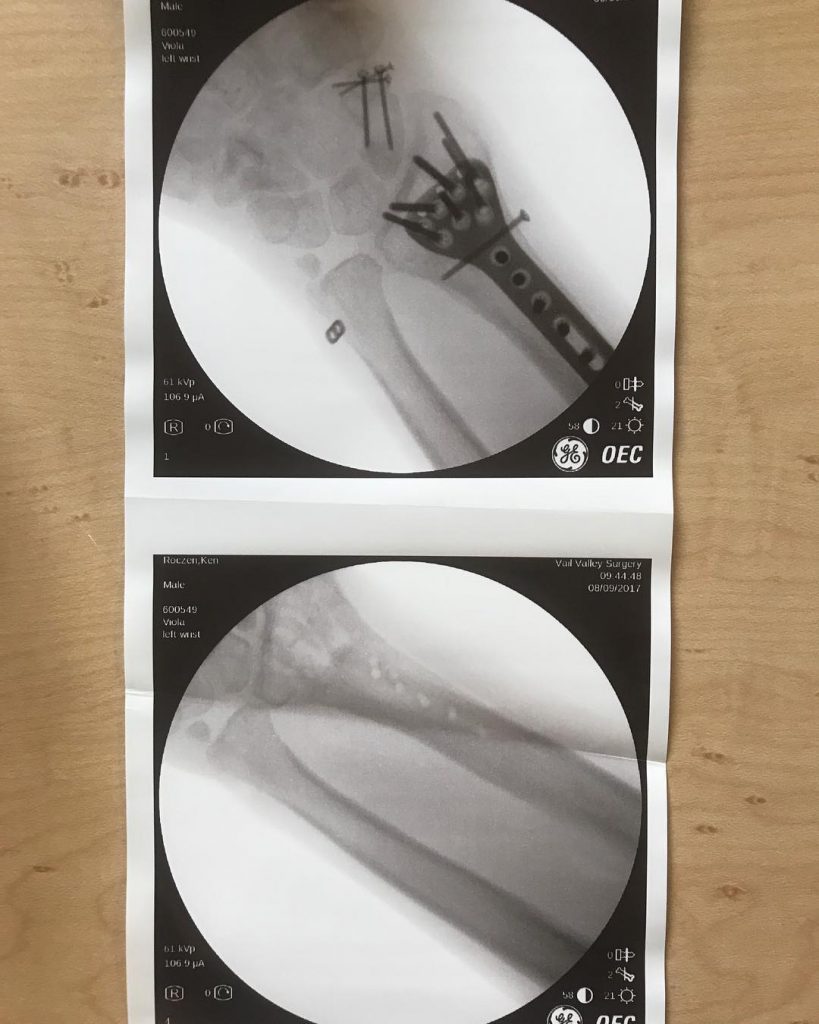

Overall things are going very well. My healing process has actually become quite a bit shorter than we originally thought. The only thing that’s not fully healed yet is my radial head [end end of the radius bone, where it meets the elbow]. It’s doing really good but not to 100% yet. My wrist is fully healed but I still have a little stiffness and pain so we’re still cranking away on that. I got some of the hardware taken out about eight or nine days ago, so my incision is still healing from that but I felt it was necessary to hopefully allow me to ride pain-free. Otherwise, I’m doing very well and happy with how things are coming along.